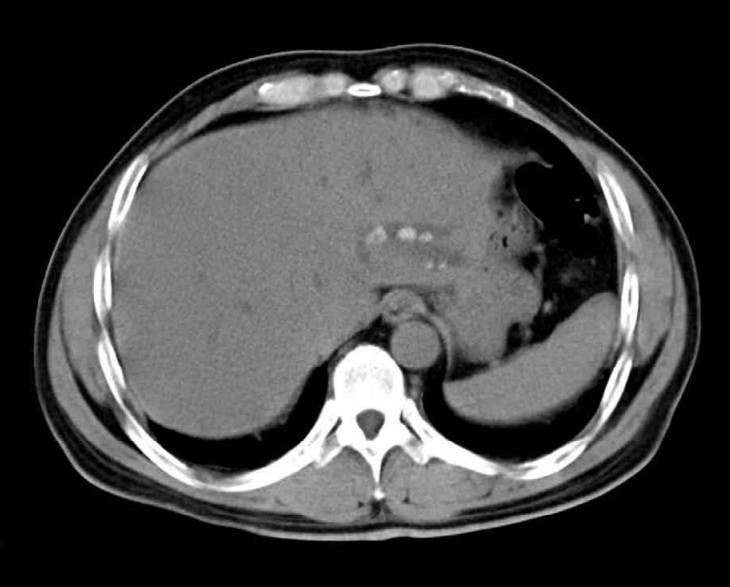

53세 여자가 1일 전부터 배가 아파서 응급실에 왔다. 5년 전부터 1년에 두세 번씩 같은 증상이 있었으며, 그때마다 항생제로 치료를 받은 후 좋아졌다고 한다. 혈압 100/60 mmHg, 맥박 110회/분, 호흡 19회/분, 체온 38.6 °C이다. 공막이 노랗다. 왼쪽 윗배에 압통이 있으나 반동압통은 없다. 혈액검사 결과는 다음과 같다. 복부 컴퓨터단층촬영 사진과 복부 자기공명담췌관조영 사진이다. 치료는?

CT: Hepatolithiasis in left hepatic lobe

• CT상 간 좌엽에 하얀 담석과 간내담관의 확장 소견이 관찰되며, MRCP상 left intrahepatic bile duct의 stricture 소견이 관찰된다.

• 임상증상, 혈액검사, 영상소견을 종합할 때 간내담석으로 인해 담관염이 발생된 것으로 생각된다. 환자는 5년 전부터 같은 증상이 반복되었으며, MRCP상 간내담관의 협착 소견이 확인되므로 담관염이 만성적으로 재발함을 알 수 있다. 따라서, 간내담석에 의한 재발성 화농성 담관염(recurrent pyogenic cholangitis)으로 진단가능하다.